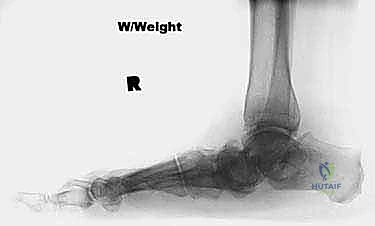

* تشوه ملحوظ في شكل القدم: تسطح كامل للقوس، وانحراف واضح للكعب نحو الخارج (Valgus).

* تصلب مفاصل القدم (Rigidity)، حيث لا يمكن للطبيب إعادة القدم إلى وضعها الطبيعي يدوياً أثناء الفحص.

كما ذكرنا سابقاً، الطريقة الكلاسيكية تتطلب شقاً من الداخل وشقاً من الخارج. في حالات القدم الروحاء الشديدة (انحراف الكعب للخارج)، يكون الجلد الخارجي منكمشاً وقصيراً.

عندما يقوم الجراح بتصحيح هذا الانحراف وإعادة القدم لوضعها المستقيم، فإن الجلد الخارجي يتعرض لشد عنيف جداً. إذا كان هناك جرح (شق جراحي) في هذا الجلد المشدود، فإن تدفق الدم إليه سيقل بشكل خطير، مما يؤدي إلى مضاعفات كارثية مثل:

تُجرى هذه العملية المعقدة تحت التخدير العام أو النصفي، وتستغرق عادة ما بين ساعتين إلى ثلاث ساعات. يحرص الأستاذ الدكتور محمد هطيف على اتباع بروتوكول جراحي دقيق لضمان أعلى نسب النجاح:

الخطوة الأولى: التجهيز والشق الجراحي

يتم وضع المريض في وضع الاستلقاء، ويتم استخدام عاصبة (Tourniquet) لتقليل النزيف. يقوم الدكتور هطيف بعمل شق جراحي واحد منحني على الجانب الإنسي (الداخلي) للقدم، يمتد من أسفل الكعب الداخلي وصولاً إلى العظم الزورقي.